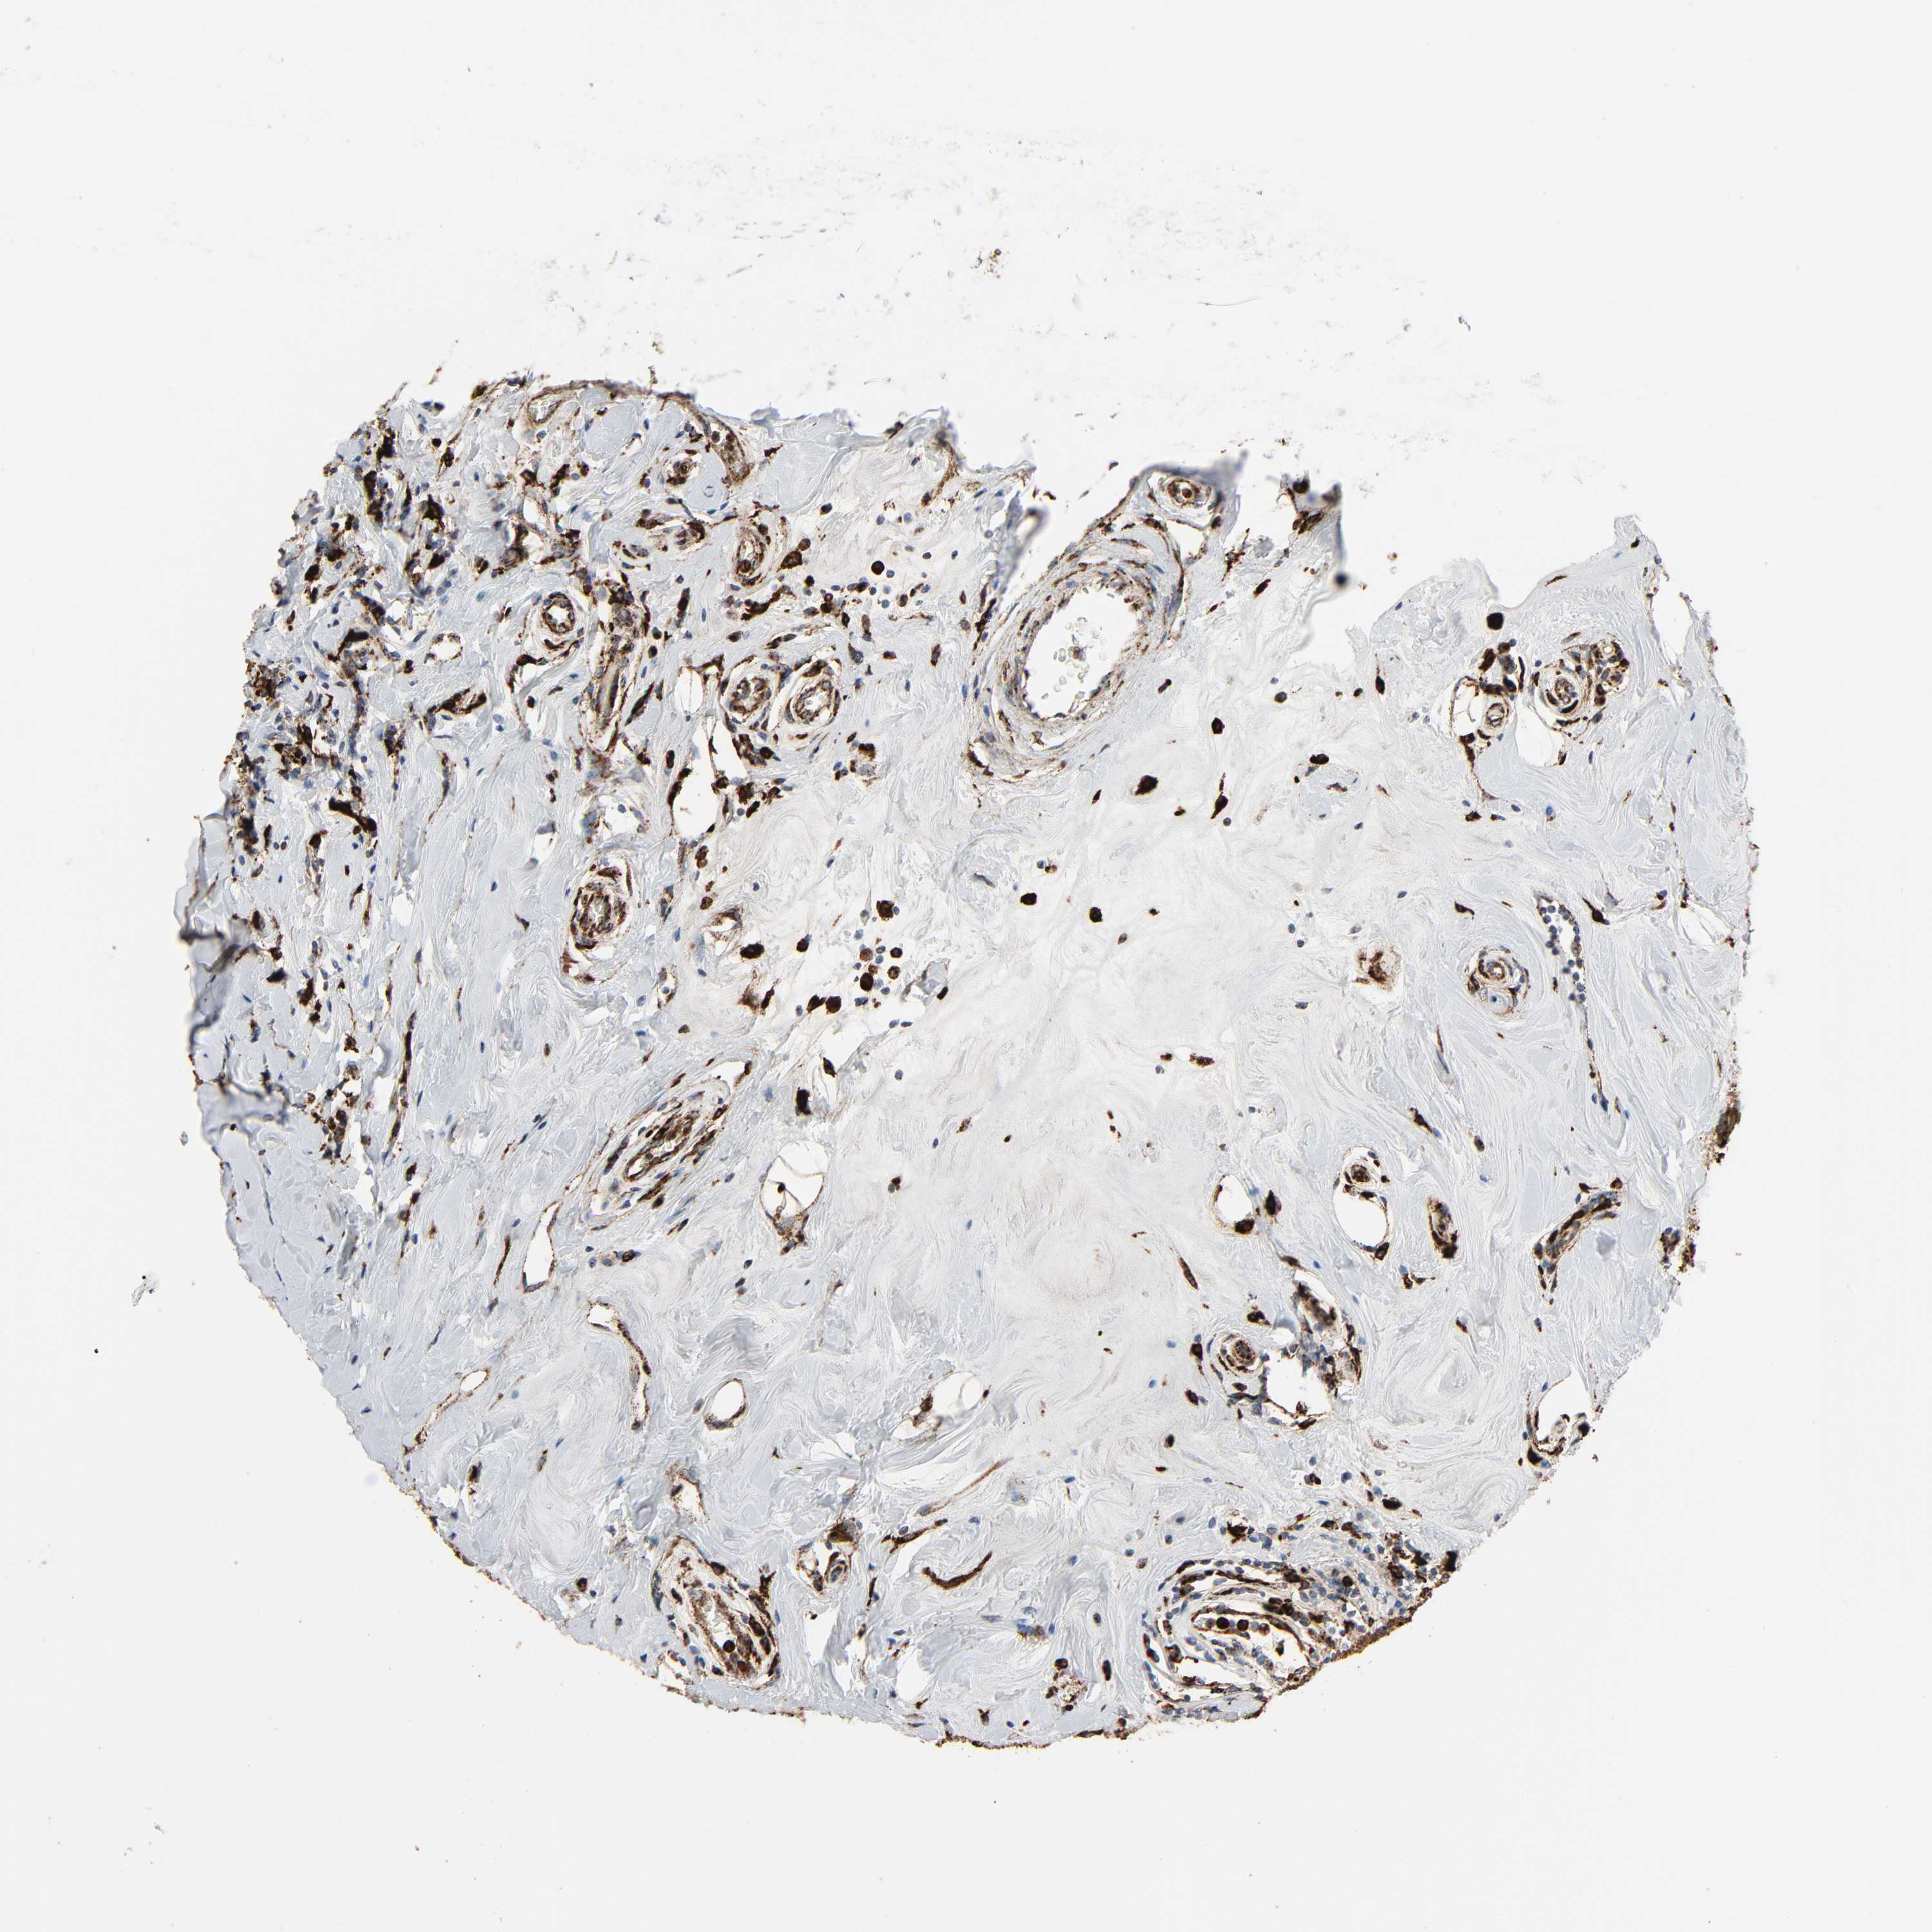

CANCER BREAST CANCER Show tissue menu

BRCA TCGA BRCA VALIDATION PROTEIN EXPRESSION